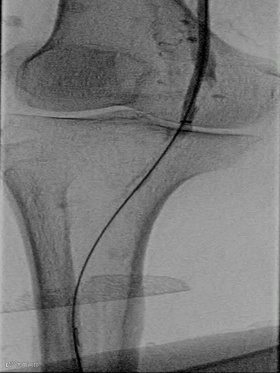

手术过程